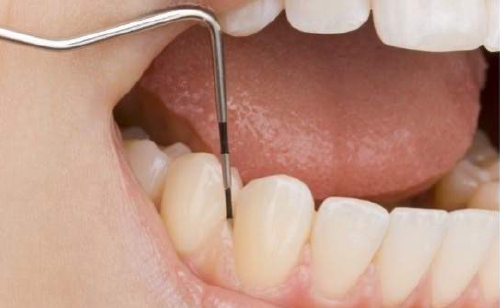

歯肉炎や歯周病になっていないか検査をします。歯と歯茎の間を触って確認し記録していきます。

歯肉炎・歯周病を診るための検査です。定期検診では、歯周病の治療にて炎症が落ち着いた場所の経過を診たり、新しく炎症を起こしていないか診ていきます。

| 治療に伴うリスク | ・歯茎の炎症が強いと歯石を取る際に出血することがあります ・処置後歯石がとれたことにより、歯がしみることがあります ・歯石がとれたり歯茎の炎症が引くことで、歯と歯の間に隙間ができ、息が漏れ発音しにくいと感じることがあります ・歯茎の炎症が軽減すると歯茎が引き締まり、歯が長く見えることがあります |